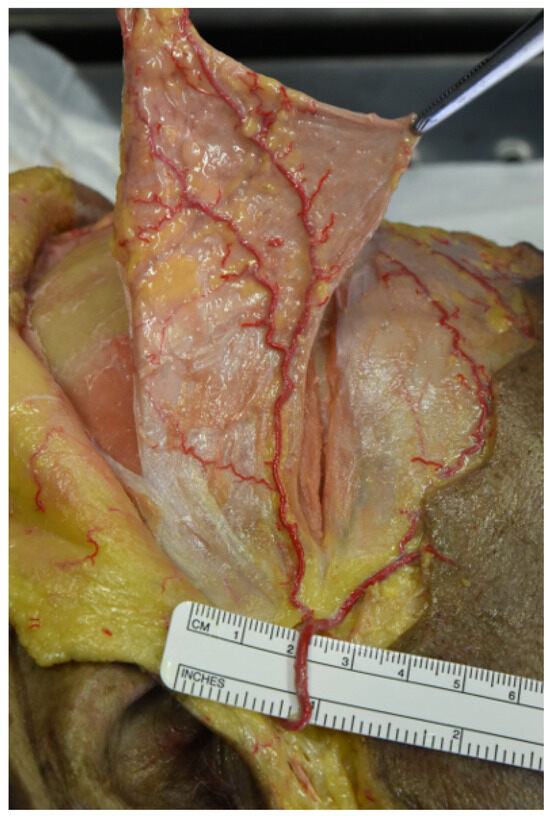

At this point, galeo-pericranial flaps were elevated and detached from the temporal region (Figure 4).

The maximum width of the flaps with superficial temporal fascia included was 15 cm, the extension of the flap depended on the vascular pattern of the superficial temporal network for each donor.

The average galeo-pericranial layer of these flaps ranged between 6 and 8 cm × 9 and 13 cm, which was sufficient to cover the mandibular defects reproduced.

Figure 4. Elevation of the flap pedicled on the parietal branch of the superficial temporal artery (STA). The figure shows the elevation of the galeo-pericranial flap, including part of the superficial temporal fascia, pedicled on the parietal branch of the superficial temporal vessels.